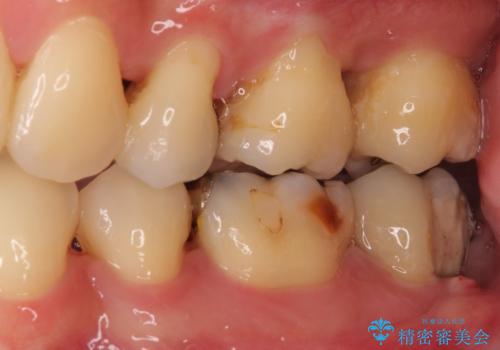

治療期間を短縮することが可能となった、ストローマン社のSLActiveというインプラントを使用し、抜歯からクラウンが装着されるまで6ヶ月という短期間で終えることができました。

咬み心地はもちろん、清掃性もご自分の歯とほとんど変わらない状態となり、患者様には大変満足していただきました。